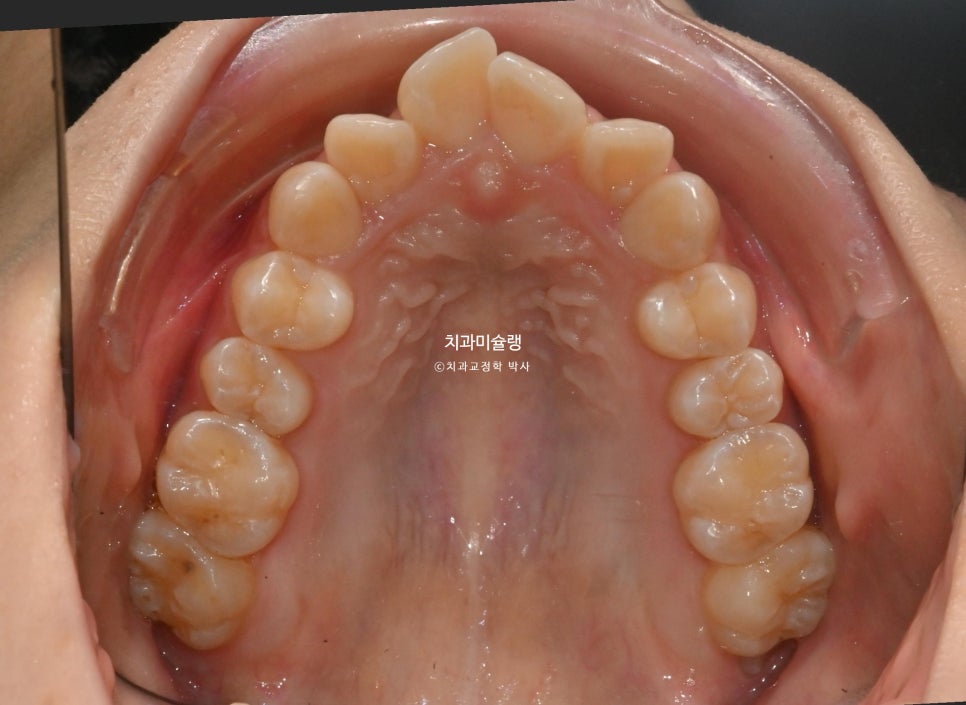

아래 앞니가 1개 선천적으로 없는 3전치 입니다.

어금니는 가지런한 편입니다.

따라서 치간삭제를 무리되지 않는 선에서 여러군데 함으로써 앞니 배열될 공간을 만들어 배열 위주의 교정을 하기로 했습니다.

아래 앞니가 3개인 경우, 위 앞니 중심선이 아래앞니 가운데 치아의 정중앙에 오게 됩니다.

위 앞니 부터 작은어금니 까지 사이사이에 0.5mm씩의 치간삭제를 했습니다.

부위당 0.5mm 이상의 치간삭제를 처방하지 않는다는 이야기 입니다.

한부위 0.5mm 의 치간삭제를 했다는 말은, 양옆 치아에 각각 0.25mm씩 치아의 최외곽층 에나멜의 가장 풍융한 부위를 마모시킨다는 이야기 입니다.

치아의 평균 에나멜 두께를 고려하면 보수적이고 안전한 양입니다. 물론 사람마다 에나멜 두께가 조금씩은 다를 수 있으니 이부분은 주치의가 잘 살펴봐야 하는 부분이죠.